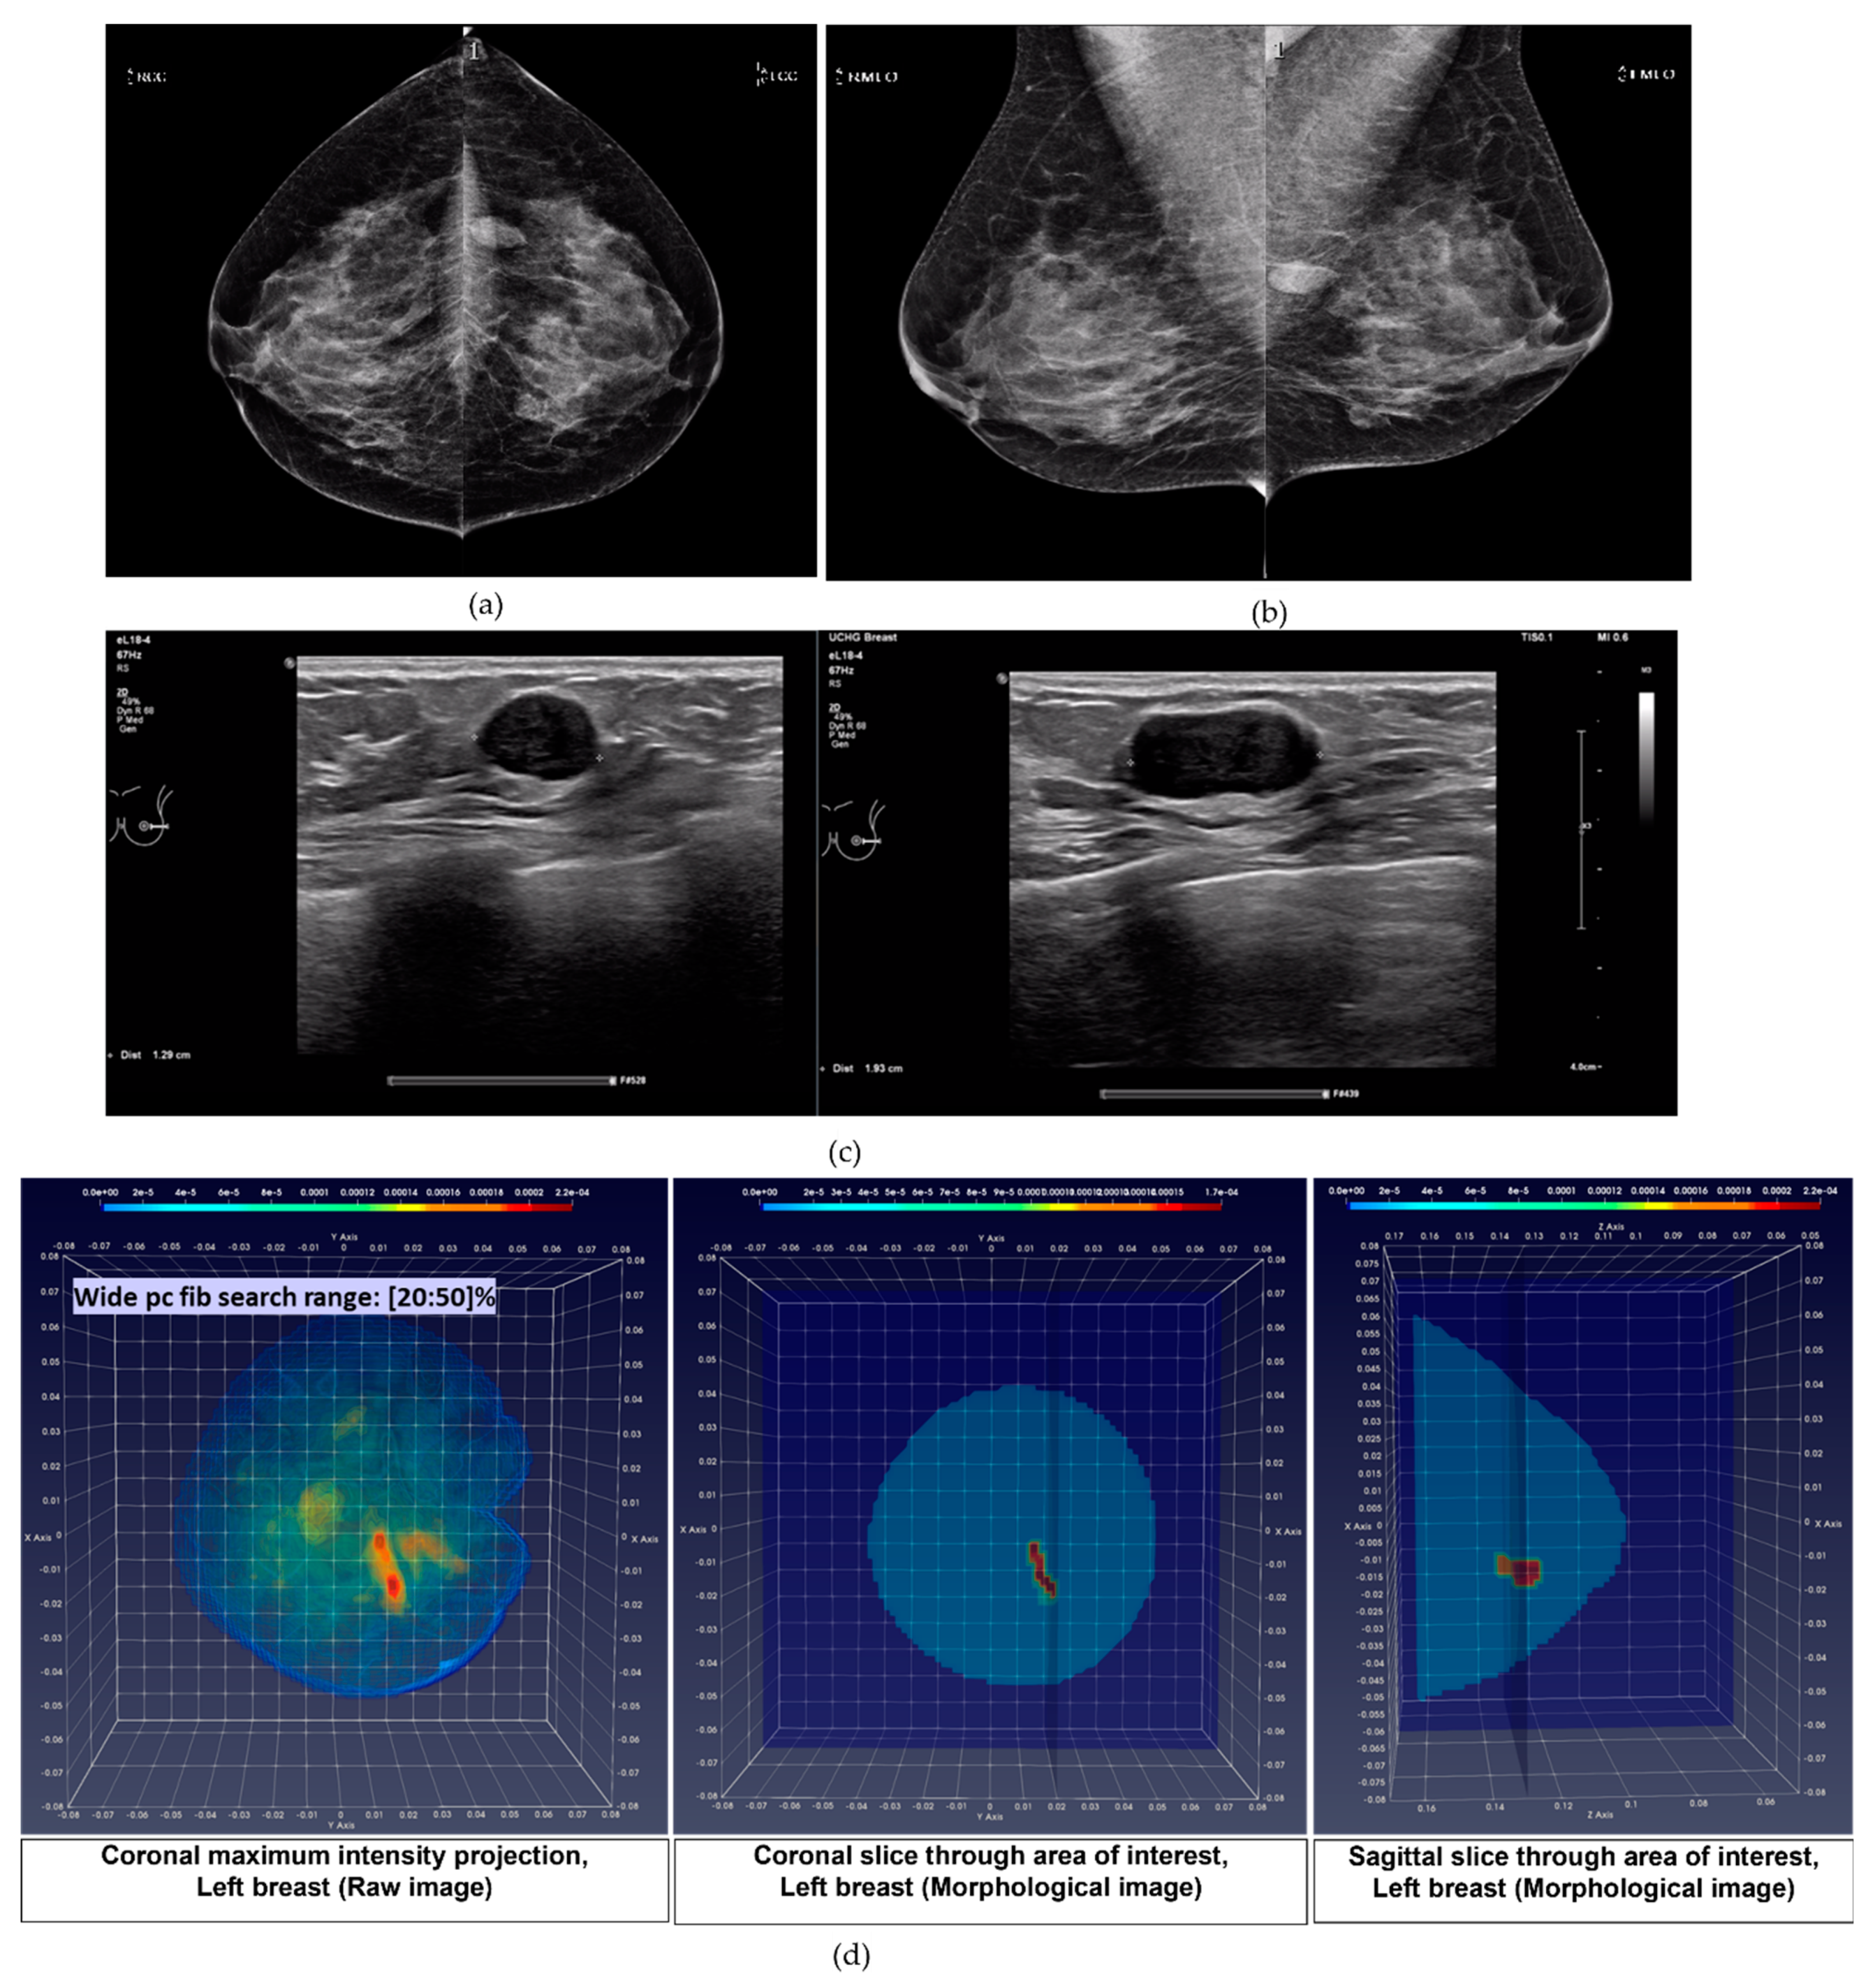

- Patient 031: Group 3: 38-years old patient with a Fibroadenoma of size 19 mm (Ultrasound) in the lateral Left Breast. Breast density: BIRADS Category c, VBD = 10.8%.

- pc_fib parameter setting in multiple search ranges: A large variability exists in the dielectric properties of each breast tissue type over the population, as demonstrated by multiple studies involving ex-vivo dielectric measurements of a large sample of excised breast tissues [18,19,20,21]. Considering that the full dielectric map of each breast cannot become practically available, data-driven techniques are employed in the Wavelia QIF to deduce the unknown dielectric properties of the healthy breast tissue in each breast, by assessing the pc_fib parameter. The pc_fib parameter, which is involved in the formulation of the illumination vector of the MBI sensor array, is physically associated with the percentage of fibro-glandular tissue along the propagation path within the breast, from a given transmitting antenna to the interrogated imaging pixel and back to a given receiving antenna, as defined in Equations (1)–(3). The Wavelia QIF generates a set of parametric MBI radar images under various assumptions on pc_fib. The generated set of parametric images is further evaluated in terms of focusing, using the image curvature [22,23] as a focusing quality measure. To better handle the heterogeneity of the breast and potentially better reveal the non-uniform angular response of the breast lesions to MBI, the pc_fib parameter setting is performed independently in each azimuthal imaging sector, while employing multiple search ranges. In the Wavelia QIF, X1 wide and X2 narrow pc_fib parameter search ranges are systematically employed for image formation, thus a total number of X = (X1 + X2) MBI images are formed per patient’s breast.

- Wide pc_fib search range #2 (W2): pc_fib ϵ [20 30 40 50]%

- Breast Lesion sizing: by means of fitting an ellipsoid to the ROI associated with the persistent lesion detection, in the 3D MBI images that have been generated by applying either of the two wide pc_fib search ranges. The greatest linear dimension of the lesion is defined as the length of the longest axis of the fitted ellipsoid. This definition is compatible with the conventional method that is applied for sizing breast abnormalities based on 2D mammography and ultrasound images [24,33]. During the FiH clinical investigation, the Wavelia MBI system showed promise for measuring lesion size with a more favorable linear trend between MBI and post-surgery histological lesion size, compared to the results obtained for conventional imaging [14]. Two challenging patient cases in terms of breast lesion sizing are indicatively discussed in Results Section 3.2, to better highlight the status of the MBI lesion sizing method, as integrated into the current version of the Wavelia QIF.